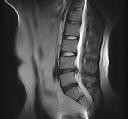

Figures 1 through 3 show sagittal and axial MRIs and a radiograph from a

77-year-old woman with leg pain when standing and walking of 1 year duration. The pain improves when she leans forward. She has been in physical therapy, taken oral analgesics, and had epidural injections with minimal relief. What is the best next step?

4. Microdiskectomy Discussion: B

The patient has lumbar stenosis of L2-3 and L3-4. She has no spondylolisthesis or instability. For her condition, spinal fusion plays a minimal role. She has no evidence of instability, and her condition can be addressed through laminectomy only. No role exists for microdiskectomy, because her disease results from a combination of ligamentum flavum hypertrophy and facet hypertrophy.